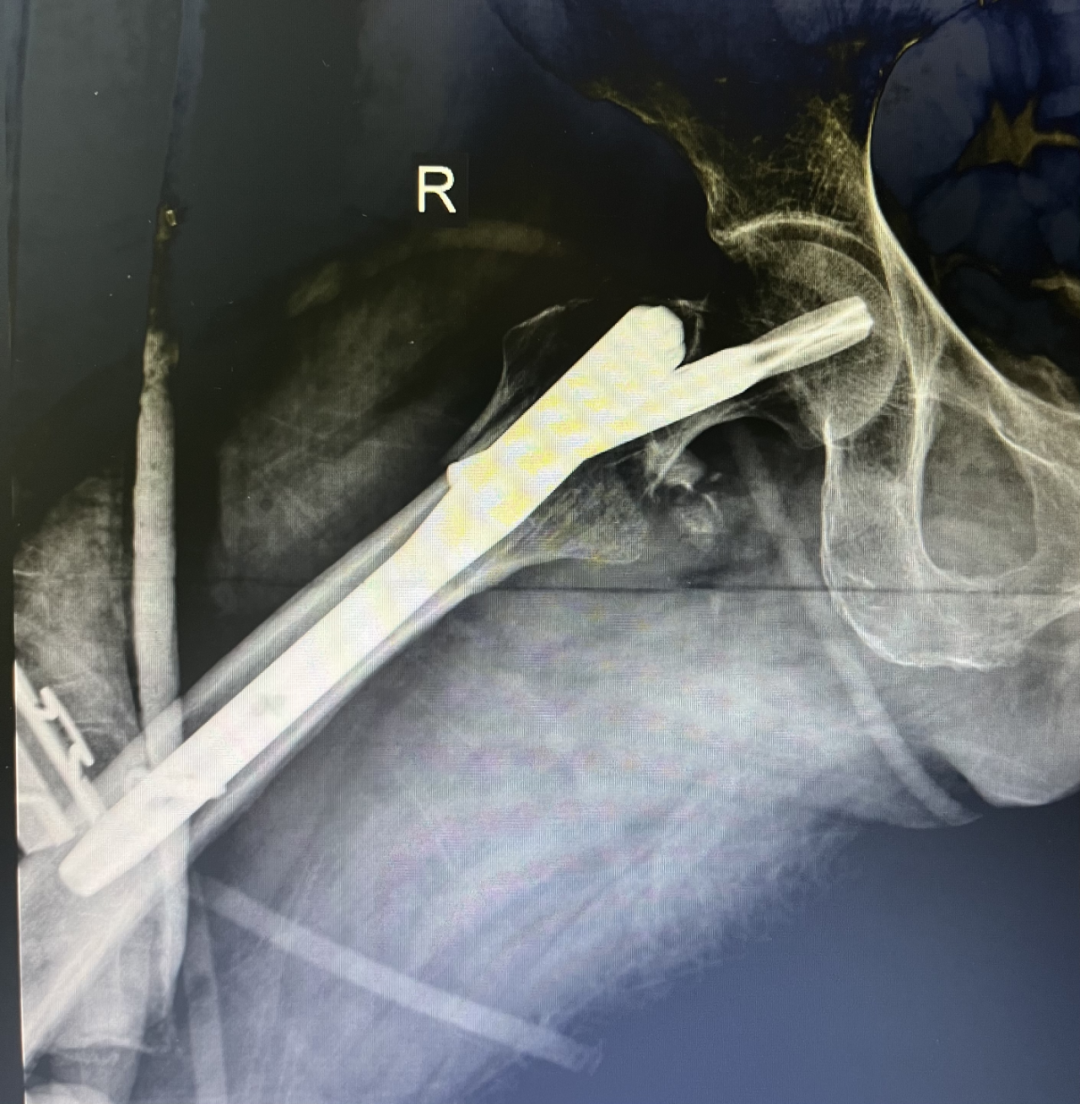

近日,我科收住一位高齡患者,孫某某,女,82歲,患者2小時(shí)前因摔傷致全身多處腫痛、伴活動(dòng)受限。入院后診斷:1.右股骨粗隆間粉碎性骨折;2.右尺橈骨遠(yuǎn)端粉碎性骨折;3.右鎖骨骨骨折;4.右肱骨大結(jié)節(jié)骨折;5.右恥骨下肢骨折;6.重度骨質(zhì)疏松。 鑒于患者屬高齡,損傷重,病情復(fù)雜,入科后科主任魏國(guó)華帶領(lǐng)關(guān)節(jié)骨科醫(yī)護(hù)團(tuán)隊(duì)積極完善相關(guān)檢查、科學(xué)制定治療方案,充分發(fā)揮中醫(yī)骨傷的治療優(yōu)勢(shì),保守與手術(shù)相結(jié)合,對(duì)右尺橈骨遠(yuǎn)端粉碎性骨折行手法復(fù)位石膏托外固定術(shù)。 排除手術(shù)禁忌后,在腰硬聯(lián)合麻醉下行右股骨粗隆間粉碎性骨折閉合復(fù)位PFNA內(nèi)固定術(shù),其余疾病行保守治療,術(shù)后經(jīng)活血化瘀、益氣養(yǎng)血等積極對(duì)癥治療,患者肢體功能恢復(fù)良好,已康復(fù)出院。 股骨粗隆間骨折是老年人常見(jiàn)損傷,俗稱人生最后一次骨折。老年人骨質(zhì)疏松,肢體不靈活,當(dāng)下肢突然扭轉(zhuǎn)、跌倒或使大粗隆直接觸地?fù)p傷,甚易造成骨折。由于粗隆部受到內(nèi)翻及向前成角的復(fù)合應(yīng)力,引起髖內(nèi)翻畸形和以小粗隆支點(diǎn)的嵌壓形成小粗隆蝶形骨折。亦可由髂腰肌突然收縮造成小粗隆撕脫骨折。粗隆部骨質(zhì)疏松脆,故骨折常為粉碎型。 就診地址:酒泉市中醫(yī)醫(yī)院關(guān)節(jié)骨科?? ?? 門診部:二樓205診室 住院部:綜合樓6樓住院部